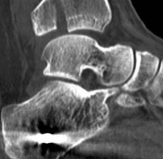

Fig 2.2-3a–h A CT scan with 3D reconstruction.

a–d Sagittal (a–b), coronal (c), and axial (d) images demonstrate displaced posterior, anterolateral, and medial fracture fragments resulting in intraarticular step and gap. The incongruent tibiotalar joint is best appreciated on the sagittal scan.

e–h The 3D reconstructed images show the external fracture anatomy and general alignment.